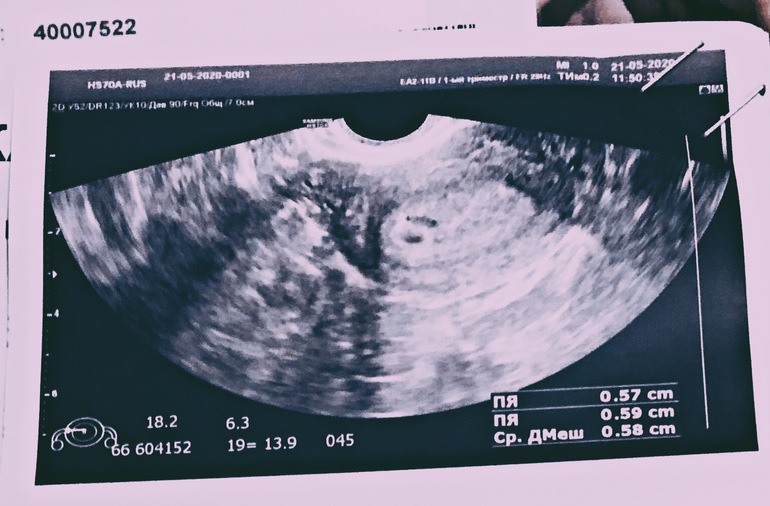

Первое узи, 22 дпо

На фото справа внизу написано ПЯ 0.57,ПЯ 0.59.

Это не два ПЯ. Это два размера одного ПЯ. И исходя из этих данных, получился Средний диаметр ПЯ 0.58 . Вон там третья строка Ср.ДМешка(средний диаметр мешка). Одного.

В самом тексте УЗИ, что написано? В матке лоцируется...... одно ПЯ, два ПЯ? Врач что пишет в заключении? Если врач видит 2 ПЯ , то это уже точно многоплодная беременность, как он может говорить, что есть ШАНС на многоплодную Б?